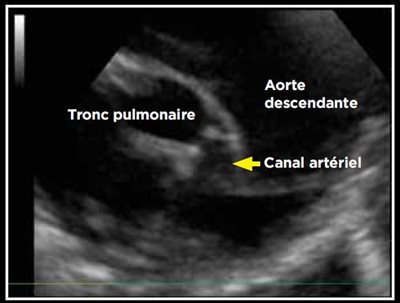

Photo 1 - Persistance du canal artériel visible en mode Doppler couleur sur une vue petit axe transaortique par abord parasternal droit.

Le canal artériel est visualisé dans 96 % des cas en mode bidimensionnel ou en mode Doppler couleur sur une coupe petit axe transaortique par abord parasternal droit (Photo 1), sur une coupe petit axe par abord parasternal crânial gauche (Photo 2), ou plus facilement sur une coupe longitudinale des gros vaisseaux (aorte et tronc pulmonaire) par abord parasternal crânial et dorsal gauche (Photo 3).